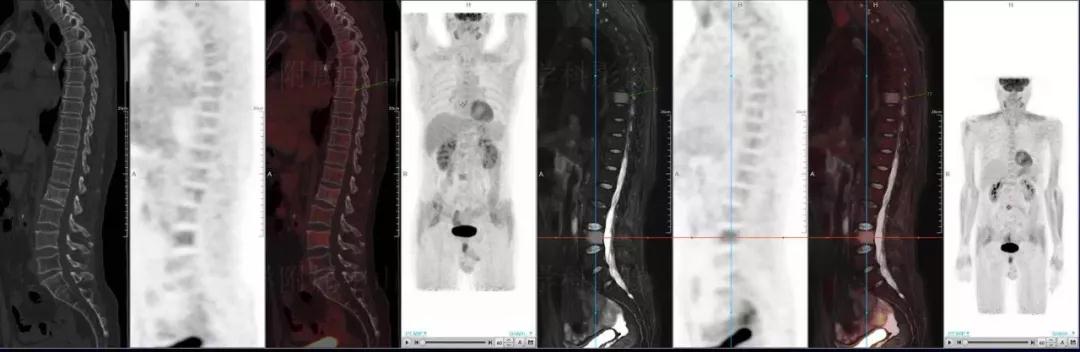

中山醫(yī)院核醫(yī)學(xué)科基于聯(lián)影“時空一體”超清TOF PET/MR的融合顯像優(yōu)勢,進(jìn)行了大量的臨床掃描,發(fā)現(xiàn)多例由MGUS向多發(fā)性骨髓瘤轉(zhuǎn)變,并從中總結(jié)出了一定的共同征象,未來可能實現(xiàn)多發(fā)性骨髓瘤的早期篩查。此外,PET/MR在多發(fā)性骨髓瘤的療效評估方面,也存在顯著優(yōu)勢。

(男性,53歲。確診多發(fā)性骨髓瘤10月。經(jīng)過7周期VCD方案化療后,現(xiàn)行療效評價。)